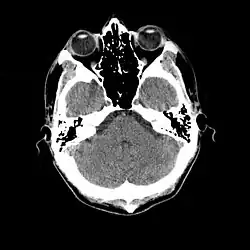

Normal human brain CT scan

A brain endocast is the imprintation of the inner features of a cranium that captures the details created from pressure exerted on the skull by the brain itself. Endocasts can be formed naturally by sedimentation through the cranial foramina which becomes rock-hard due to calcium deposition over time, or artificially by creating a mold from silicon or latex that is then filled with plaster-of-Paris while sitting in a water bath to equalize forces and retain the original shape. Natural endocasts are very rare; most of those that are studied are the result of artificial methods. Although the name implies that it is a copy of the once living brain, endocasts rarely exhibit convolutions due to buffering by the pia mater, arachnoid mater, and dura mater that once surrounded and protected the brain tissue. Furthermore, not all endocasts are created from a complete cranial fossil and subsequently, the missing parts are approximated based on similar fossils. In some cases, fragments from several fossils of the same species are used to construct a single endocast.[7]

More recently, computed tomography has played a large role in reconstructing endocasts. The procedure is non-invasive and has the advantage of being able to analyze a fossil in record time with little risk of damaging the fossil under review. CT imaging is achieved through the application of x-rays to produce tomographs, or sectional density images, which are similar to the images produced during MRI scans.[8] CT scans use slices approximately 1 mm thick to reconstruct a virtual model of the specimen.[9] This method is especially useful when a fossil cranium is occupied by a natural endocast that cannot be removed without destroying the skeletal portions of the fossil. Because the cranium and its contents are of different densities, the endocranial cavity and its unique traits can be reconstructed virtually.[8]

Radiographic technique such as computed tomographic imaging, or CT scans, coupled with computer programming have been used to analyze brain endocasts from as early as 1906.[10] Recent development of advanced computer graphics technology have allowed scientists to more accurately analyze of brain endocasts. M. Vannier and G. Conroy of Washington University School of Medicine have developed a system that images and analyzes surface morphologies in 3D. Scientists are able to encode surface landmarks that allows them to analyze sulcal length, cortical asymmetries and volume.[11] Radiologist, paleoanthropologists, computer scientists in both the United States and Europe have collaborated to study such fossils using virtual techniques.[10]